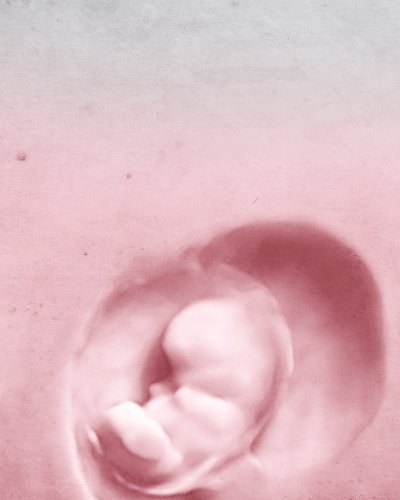

RESEARCH GIVES US LIFE

We help you to form a family

We guarantee your pregnancy or we will refund 100% of the treatment cost. Would you like to?